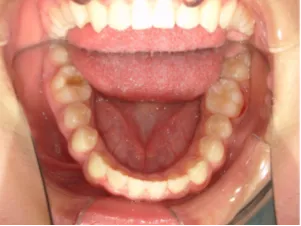

小1女子、生え変わってきても受け口なので治したい女子

治療前①小1(7y2m):初診

*上顎前歯後方傾斜、上下唇の突出、口唇閉鎖不全傾向、コンケーブなし

| カウンセリング・診断結果 | 骨格的に下顎前方位で下顎骨も大きいタイプで、上の前歯が後ろに傾斜している受け口です。 顔立ちは上下唇が突出していて口唇閉鎖不全傾向がありますが、コンケーブにはなっていません(写真①)。 機能的に低位舌があり、今後受け口を助長する可能性があります。 受け口は、上顎骨の骨格的な前方向の成長を阻害し下顎が前へ強く成長していくため、骨格的な受け口が悪化し永久歯の咬合治療が難しくなり、症例によっては外科的な治療が必要になることがあるため早期に改善し骨格的な悪化を予防する説明をしました。 |